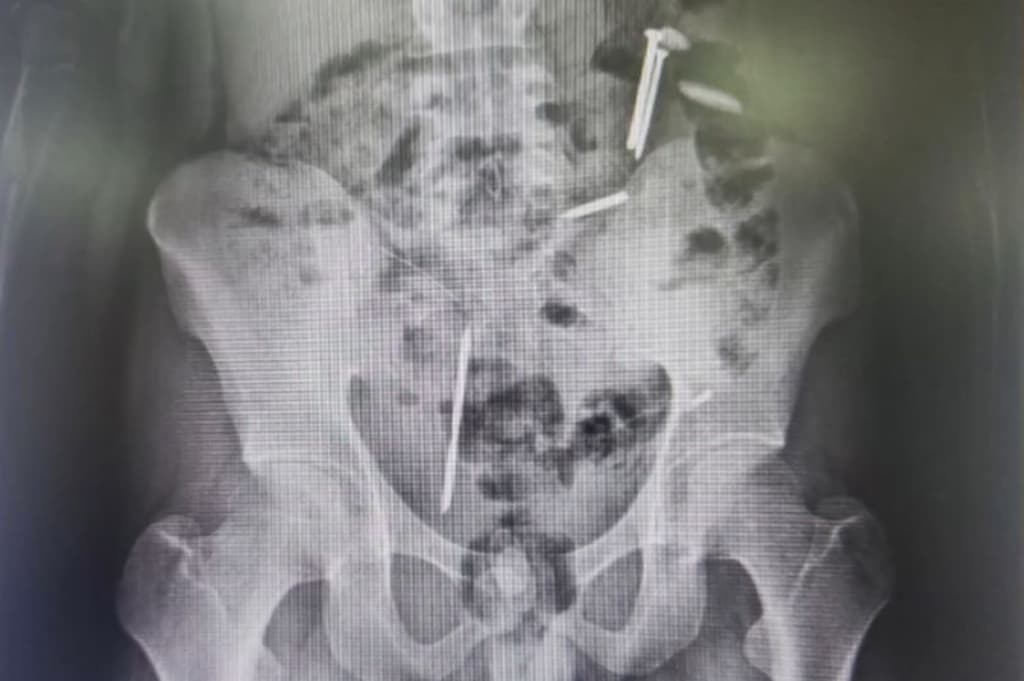

"Kami mengevakuasi saudara Mohamad Vemas atas dasar laporan kakaknya. Kami juga lakukan perekaman e-KTP dan saat dicek ronsen ditemukan benda asing dalam tubuhnya seperti dua buah paku, koin dan kawat," ujarnya, Kamis (9/4/2026).

Hasil rontgen yang dilakukan di RSJ Malang menunjukkan adanya sejumlah benda asing di dalam tubuh korban, termasuk paku, kawat, dan koin logam. Temuan tersebut membuat petugas terkejut karena jumlah dan jenis benda yang berada di dalam tubuh korban cukup berbahaya.